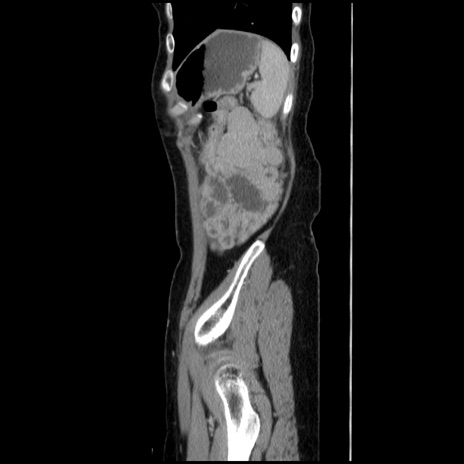

症例

【症例】40歳代 女性

【主訴】上腹部痛、嘔気・嘔吐

【現病歴】約9時間前頃から急に上腹部痛、嘔気、嘔吐が出現。改善しないため救急要請。

【既往歴】子宮頚癌(広汎子宮全摘術、放射線療法)、腸閉塞

【身体所見】腹部:平坦、軟、腸雑音亢進、上腹部を中心に腹部全体に圧痛あり。

【データ】WBC 8400、CRP 0.03